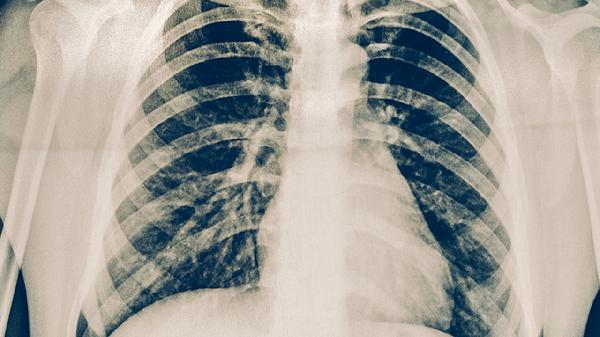

肺结核可以用中医治疗,但需与西医抗结核药物联合使用。肺结核是由结核分枝杆菌引起的慢性传染病,中医治疗主要作为辅助手段,有助于缓解症状、增强体质。常用方法包括中药调理、针灸等,但必须遵医嘱规范使用异烟肼片、利福平胶囊等抗结核药物。

中医认为肺结核属于肺痨范畴,多因正气不足、痨虫侵袭所致。治疗以滋阴润肺、补气健脾为主,常用百合固金汤、月华丸等方剂。中药成分如百部、白及、黄精等具有抑菌作用,可辅助抑制结核杆菌。针灸选取肺俞、膏肓等穴位能改善咳嗽盗汗。部分中成药如抗痨胶囊、肺泰胶囊也可配合使用。

单纯中医治疗无法彻底杀灭结核杆菌,擅自停用西药可能导致耐药性。活动期肺结核需坚持服用利福平胶囊、吡嗪酰胺片等药物6个月以上。中药调理期间应定期复查肝功能,避免何首乌等肝毒性药材长期使用。咯血患者慎用活血化瘀类中药,阴虚火旺者忌用人参等温补药。

肺结核患者需保持居室通风,饮食宜高蛋白、高维生素。适当食用银耳、山药、梨等润肺食材,避免辛辣刺激。中医治疗期间仍需隔离痰菌阳性者,规范处理痰液。若出现药物性肝损伤或过敏反应,应立即停用中药并就医。中西医结合治疗需在传染病专科医生指导下进行。